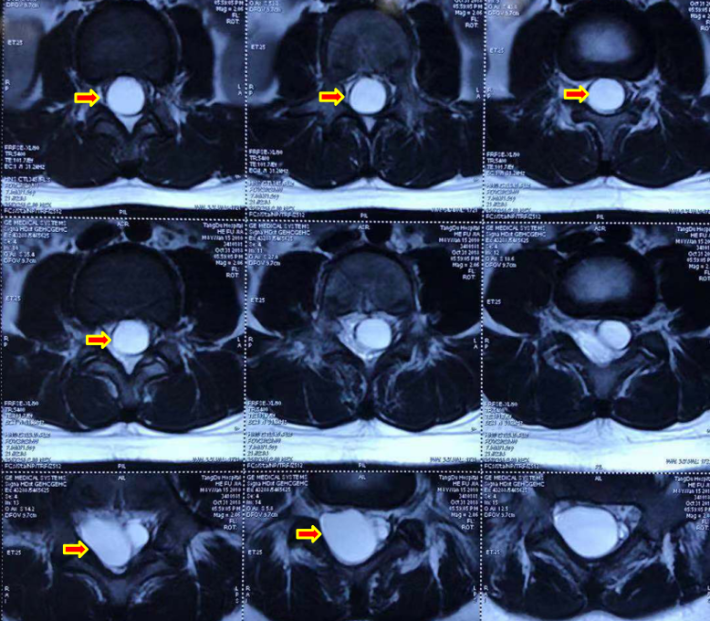

男,8岁大小便失禁伴双下肢肌力下降25天小便失禁为突出症状诊断:骶管囊肿、脊髓圆锥中央管扩张?表皮样囊肿?

本例脊髓圆锥及终丝呈囊性扩张,术中探查未见表皮样囊肿成分

存在脊髓栓系,终丝剪断部位尽量接近硬膜囊末端,多数情况下有马尾神经附着,需翻转终丝,多角度仔细观察剥离,防止误伤。